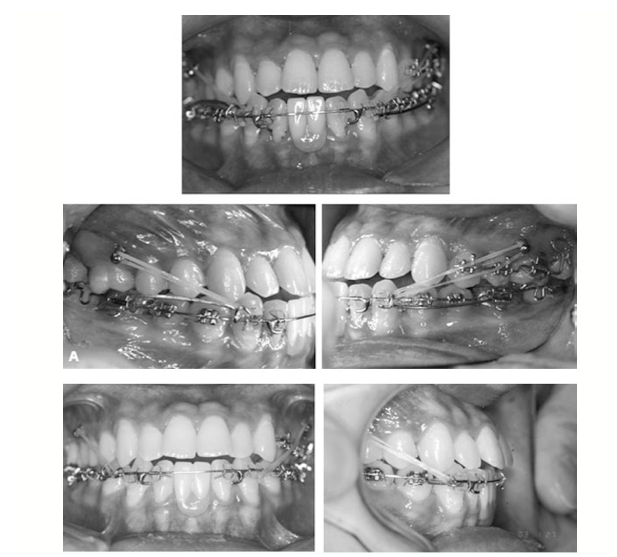

Neste artigo de 2005, publicado pela Angle Orthodontist, pelos autores Kyurhim Chung, Seong-Hun Kim e Yoonah Kook, da Korea Society of Speedy Orthodontics, Seoul, South Korea, Department of Orthodontics, The Catholic University Korea, Uijongbu, Seoul, South Korea. Mostra a aplicabilidade de um Micro implante na distalização inferior para correção de uma má oclusão de classe III.

O artigo descreve o tratamento em um paciente de 16 anos de idade com uma má oclusão Classe III e dois incisivos centrais inferiores ausentes. O plano de tratamento consistiu em forma de distalização assimétrica  inferior dos dentes e recuperar espaço para um trabalho protético anterior inferior.

C-implantes foram utilizados como elemento de ancoragem para utilização de elásticos intermaxilares Classe III. Os dois microimplantes C-ortodônticos (C-implantes) foram colocados nos espaços interdentais entre os pré-molares e molares superiores segundo primeiro. O desenho especial da cabeça C-implante o que minimizou a irritação gengival durante o tratamento ortodôntico.

Jigs deslizantes foram aplicados sobre o fio para a distalização dos dentes inferiores posteriores. A sobremordida ideal e o overjet foram obtidos com a distalização em todo o arco dentario inferior, que chegou a sua posição correta com os C-implantes de ancoragem, o que contribuiu para uma melhora no equilíbrio facial.

Levou 15 meses para tratar este caso. A aplicação deste novo microimplante, considerações para a selecção do protocolo, e a sequência de tratamento foram apresentados pelos autores.

Os autores concluíram que a ancoragem absoluta pode ser usado com um gancho para a utilização de elásticos intermaxilares em casos em que a extrusão de dentes de ancoragem deva ser evitado. O C-implante pode criar ancoragem absoluta e um amplo espectro de aplicações clínicas devido à sua concepção particular. Mais pesquisas e estudos sobre a mecânica com C-implante são necessários para estabelecer o momento da força ortodôntica ou ortopédica, combiná-lo com o tratamento ortodôntico com várias mecânicas, e  determinar as diretrizes para o tratamento em pacientes adultos com complicações sistêmicas.